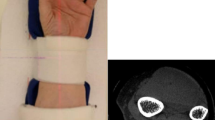

APART from the extreme criterion of bone fracture, there is no definitive measurement of bone adequacy in terms of strength in relation to function. Comparison of bone mineral is usually made on the basis of age1 or sex2 without regard to the size or the physical status of the individual. This is in spite of Galileo's observation that the weight of a body is a function of the cube of its diameter whereas the strength of a bone is a function of the square of its diameter3. Galileo also conceived that a constant sized bone would support more weight if it were made of a stronger material, but did not seem to be aware that bones are subject to change in density. This is rather surprising as he discussed at some length the density of various substances. We now know that bone density varies and that the strength of both trabecular4 and cortical bone5 increases with density.